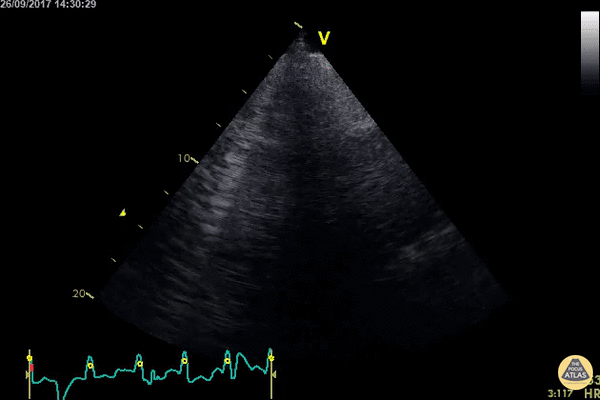

Pulmonary - Confluent B Lines

WCUME 2017 Submission for "Best POCUS" An acutely dyspnoeic patient presents with ventricular tachycardia and has no response to initial chemical cardioversion. Lung POCUS shows widespread bilateral confluent B lines indicating acute pulmonary edema. Unstable tachycardia terminated using synchronized electrical cardioversion. Dr. Cian McDermott - Dublin, Ireland